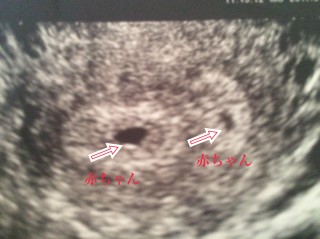

小さな黒い点が赤ちゃんです。無事にすくすく育ってます

初めて双子を妊娠。 最初はわからなかったけどよく話を聞いたら2つの命を大事に育てないとねと言われました。